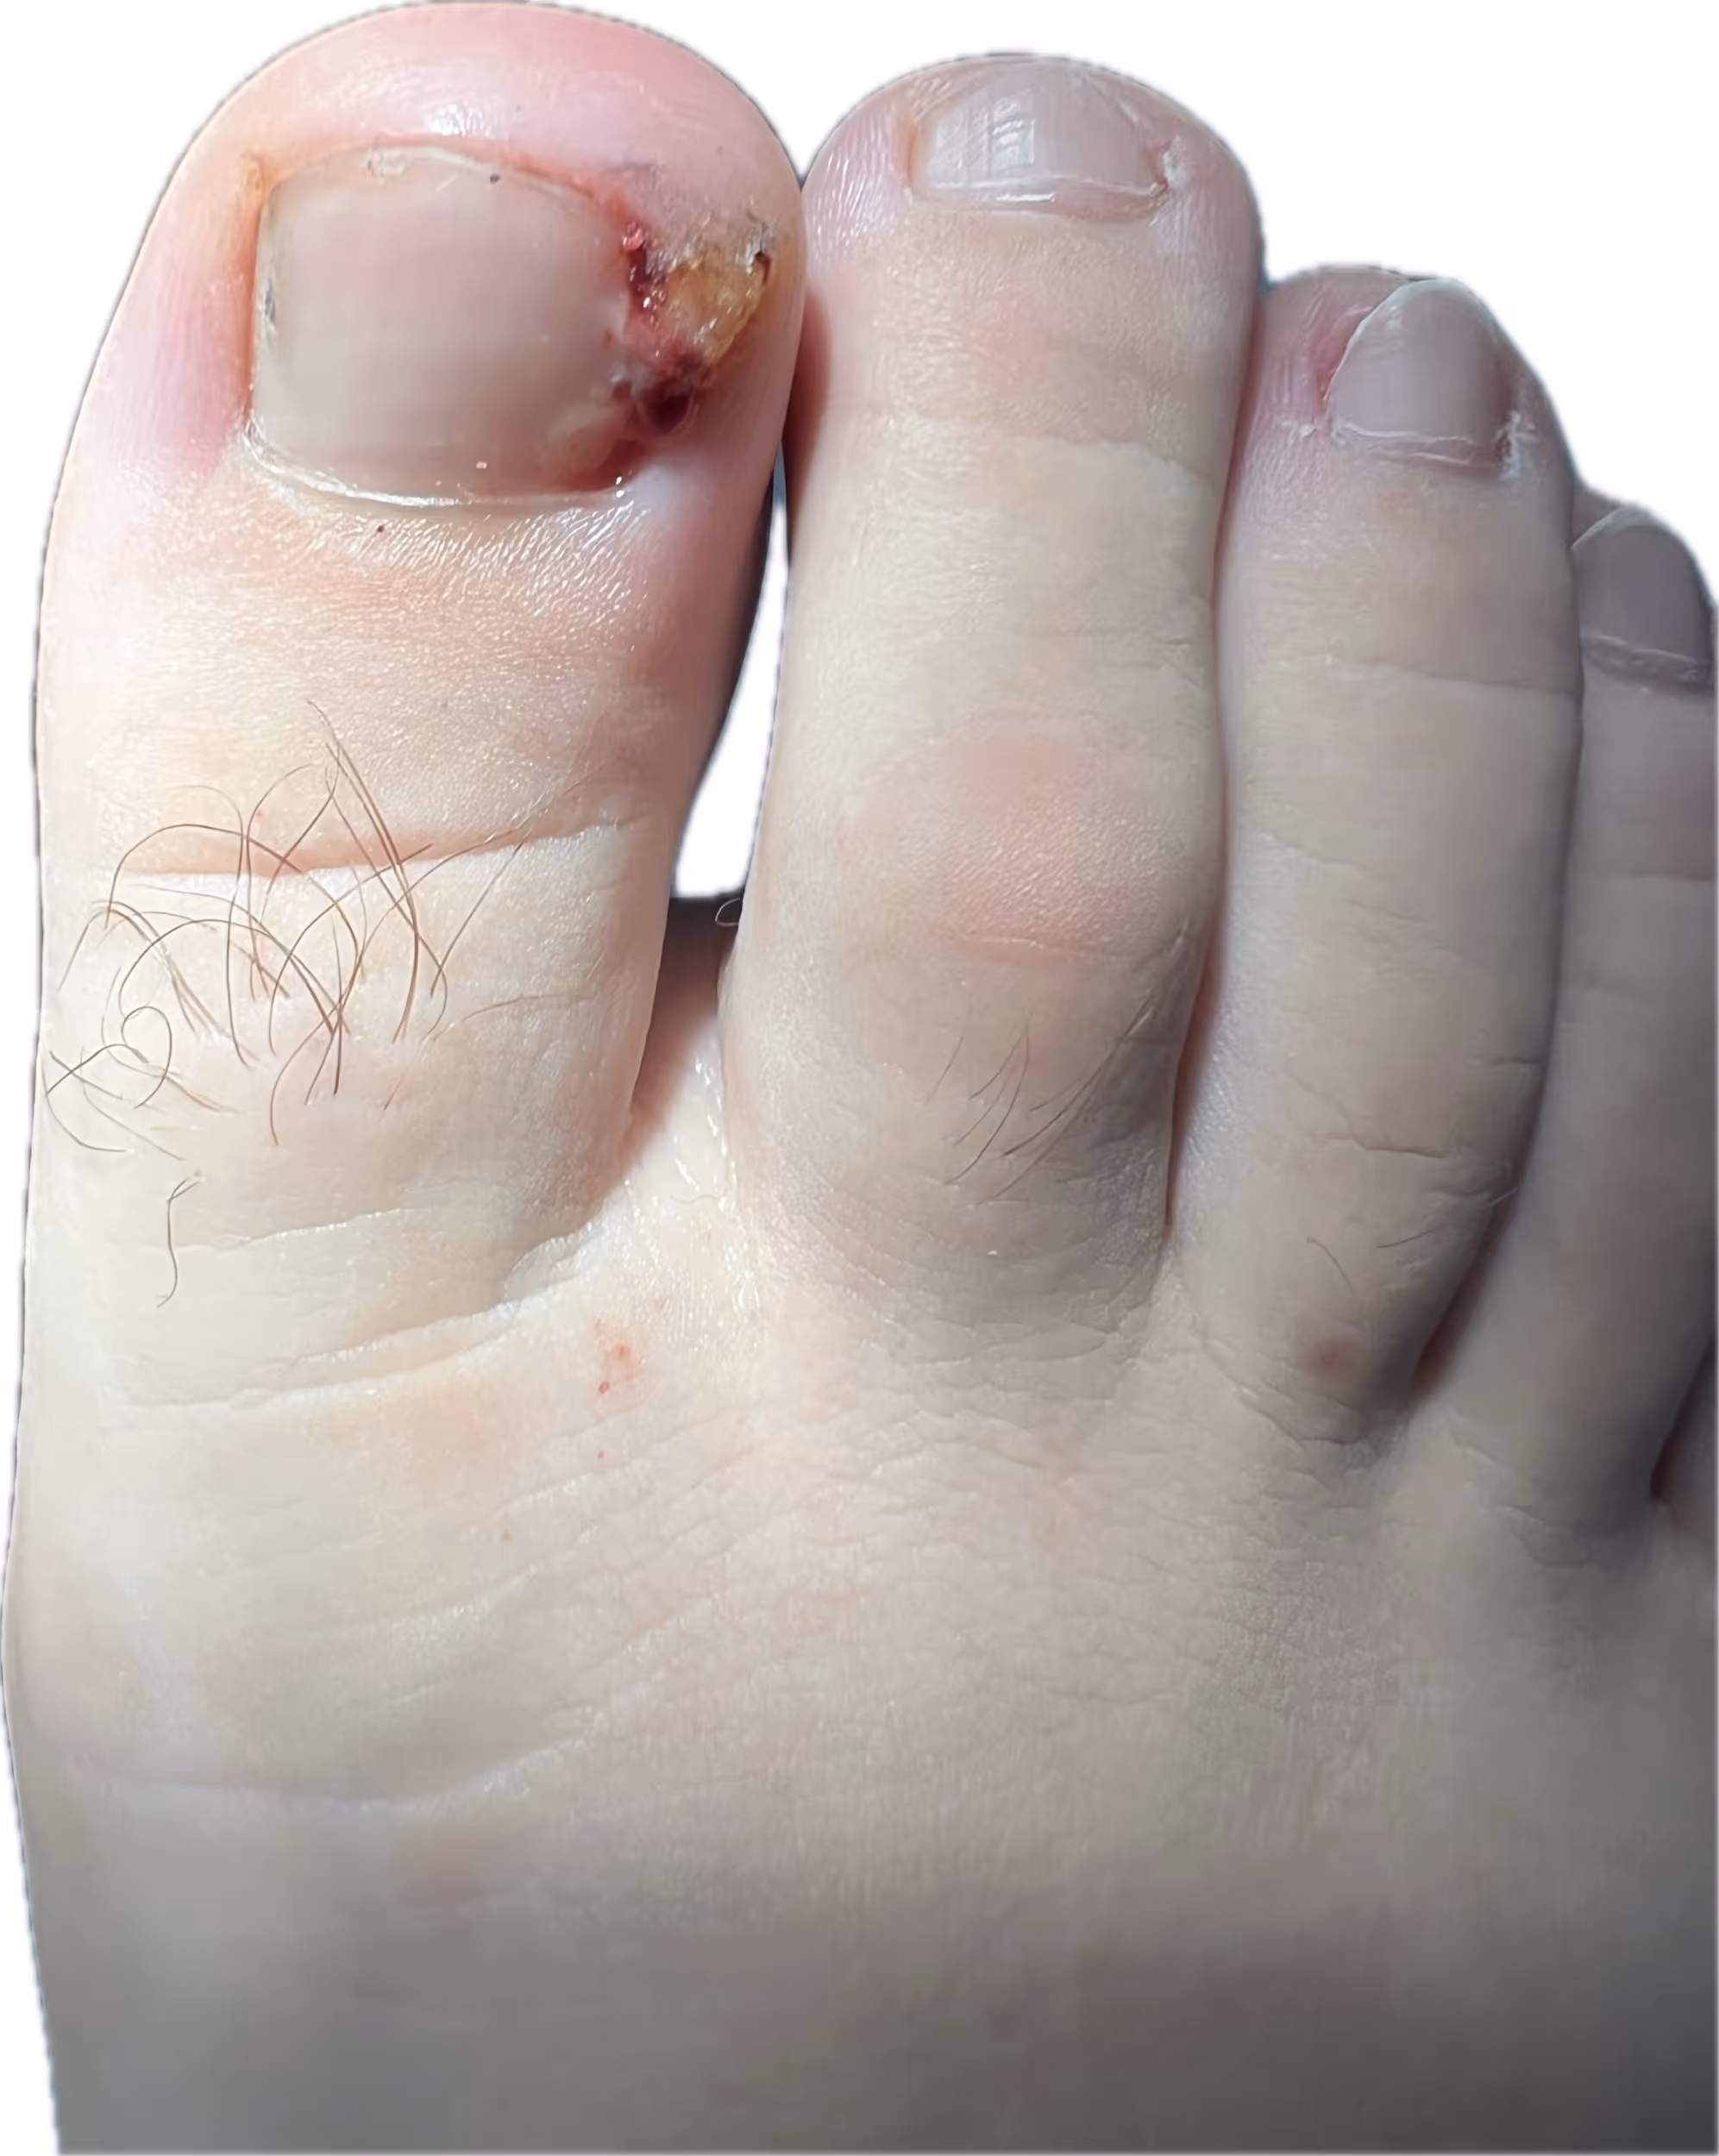

¿Vives con miedo a que alguien te pise? No, no tienes que acostumbrarte a ese dolor punzante. Una uña encarnada no se cura "cortándola más corto" en casa; de hecho, eso suele empeorarla. La clave no es quitar la uña, sino corregir el canal por donde crece. Descubre los procedimientos definitivos y sin dolor que te permitirán volver a usar tus zapatos favoritos sin molestias.